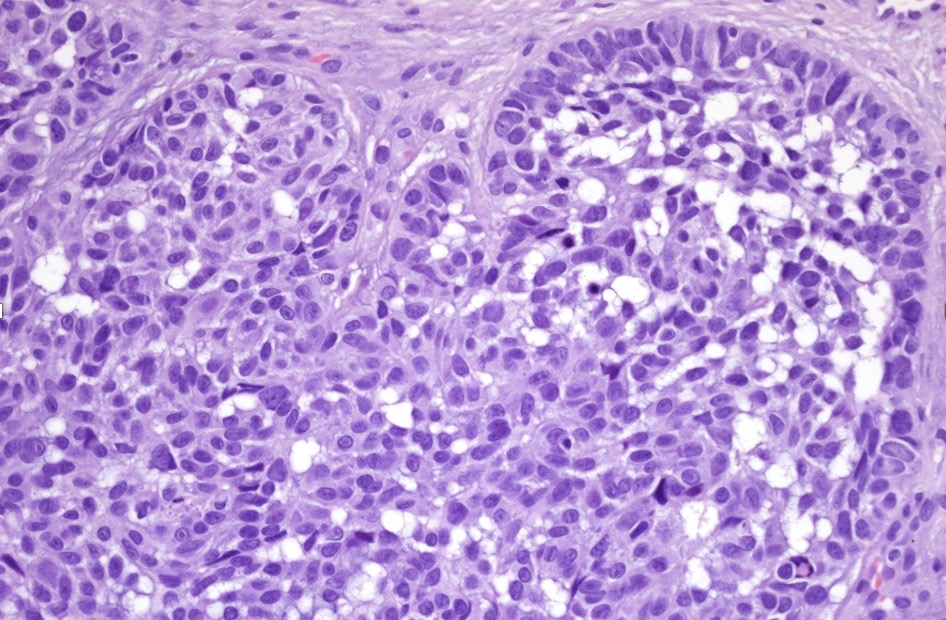

An exceedingly rare collision tumor composed of an admixture of squamous cell carcinoma/basal cell carcinoma/trichoblastoma respectively and melanoma. Although most appear to have behaved in a benign fashion, a malignant basomelanocytic tumor is illustrated below. More cases will be need to be stidies/published before the true biological behavior of this group of tumors can be satisfactorily elucidated. I think that complete excision should be the rule and a careful follow-up recomended.

Basomelanocytic tumor

Squamomelanocytic tumor